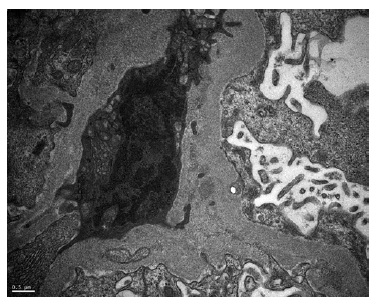

A kidney biopsy was performed, showing on light microscopy 22 glomeruli (Figure 1), one of them with global sclerosis, and five with segmental sclerosis (Figure 2). The remaining glomeruli showed swollen podocytes and segmental mesangial proliferation (Figure 2). Immunofluorescence identified mesangial and granular staining of IgA, C3c, C1q, IgM and IgG. Electron microscopy showed diffuse FPE, with only scant immune deposits confined to the mesangium (Figure 3 and Figure 44).

The severity of the nephrotic syndrome, the diffuse podocyte FPE with scanty immune complex deposition restricted to the mesangial area, and the rapid clinical response to steroids consolidated the diagnosis of lupus podocytopathy.